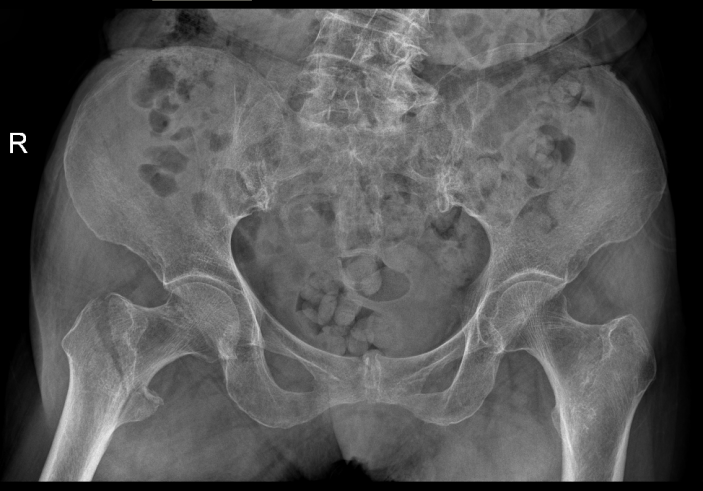

經過CT檢查發現老人家的左股骨頸骨折。此外還伴有老年性骨質疏松、高血壓病、低鈉低鉀血症等疾病。骨科吳志斌主任随即請内科、麻醉科專家會診。予監控血壓、血糖,抗骨質疏松、營養心肌等對症治療。待患者病情穩定、可耐受手術後進行手術治療。

△術前